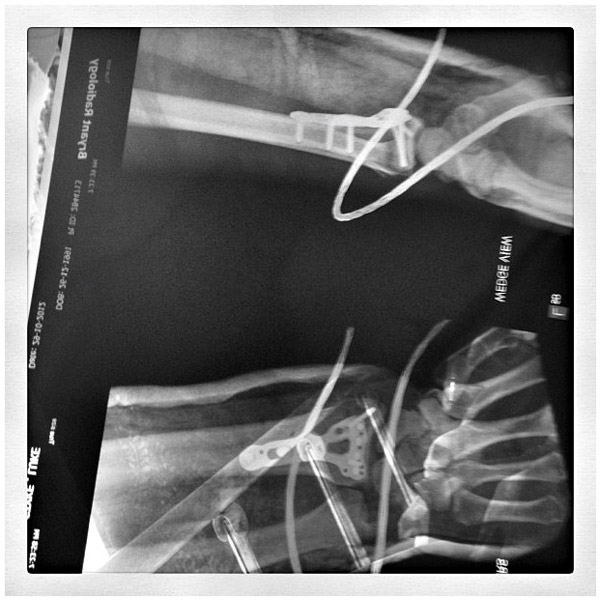

Serco Yamaha Metal Mulisha Racing’s Luke Styke busted his wrist at the Phillip Island Supercross round, and by the looks of the X-Rays taken after the operation, he might be out for some time. The team has already substituted the injured Kirk Gibbs with Luke Clout for the SX season, and with the first half already over, Team Manager Gavin Eales has confirmed they’ll just be running Clout for the final two rounds. “We won’t be replacing Styke for the remainder of the Supercross season as there’s no benefit to us – we won’t be in contention for the Lites Supercross Championship title,” said Eales. “It will just be a single-rider team with Luke Clout for the remainder of the season.” Eales also confirmed that Stykes’ surgery went well, and he’ll be back on the bike in six weeks time.